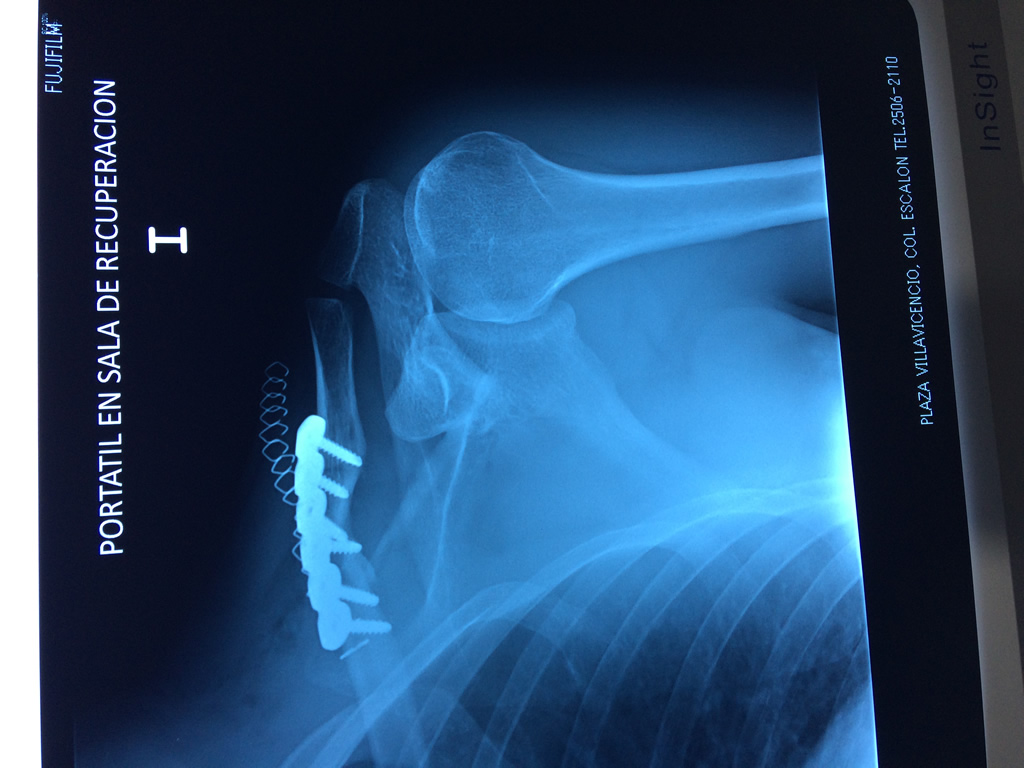

Fémur - Clavícula

La clavícula es un hueso largo, con forma de "S" itálica, situado en la parte anterosuperior del tórax. Junto con la escápula forman la cintura escapular. Se puede palpar por toda su longitud y se extiende del esternón al acromion de la escápula, siguiendo una dirección oblicua lateral y posterior.